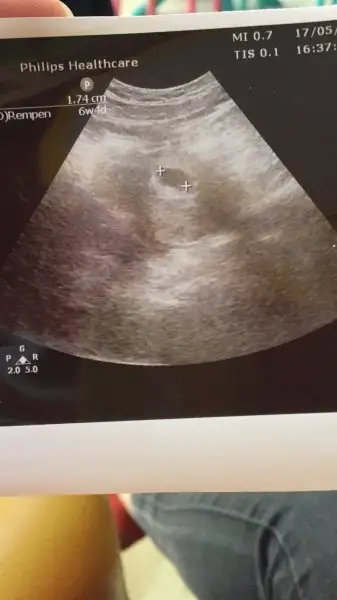

evet canım kan verıp geldım doktorum aradı 150 cıvarında cıktı beta hcg suan kac bılmıyorum ama kese olusmus durumda ıdı haftaya gıdıp kalp atısnı duymak nasıp olur umarım

Bende bilmiyorum ama doktor kalp atışları var dedi elhamdülillah. O yüzden sevinçliyim. Çarşamba tekrar gideceğim olmadı ayrı doktora da görünürüm:))))